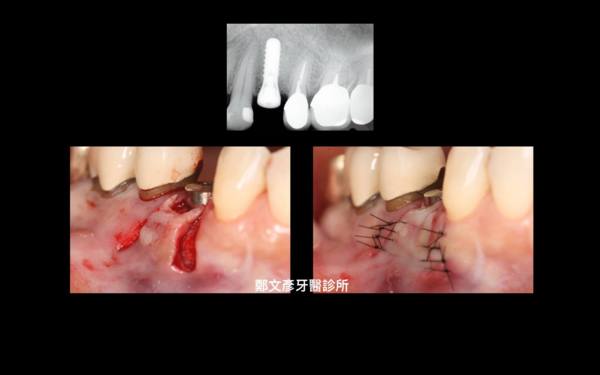

Role of granulation tissue in socket preservation

3. Role of granulation tissue in socket preservation